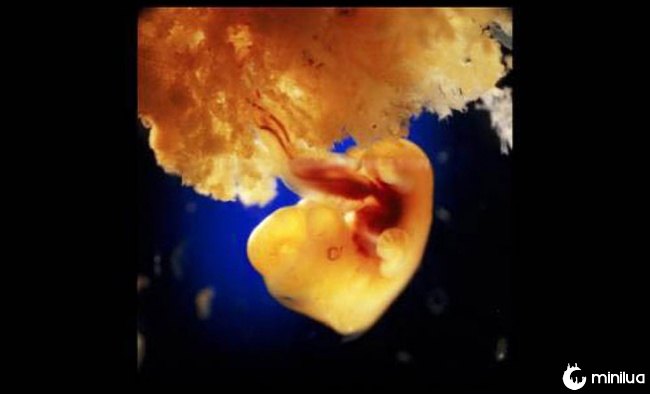

40 dias de desenvolvimento. As células externas do feto se unem à superfície solta da parede do útero para formar a placenta.